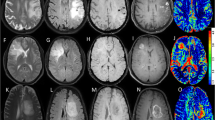

Regarding rCBVt value, for high-grade glioma (Fig. 1), the mean was 3.5 (1.8–6.13), and for low-grade glioma (Fig. 2) 1.16 (0.5–1.7) (P = 0.0001). There is statistical significance for differentiation between low- and high-grade glioma (Fig. 3) (shown in Table 2).

A 30-year-old male presented by amnesia, slurred speech and right hemiparesis since 1 month. a Axial T2 showing left tempero-parietal large ill-defined SOL surrounded by moderate vasogenic edema. b T1 post Gd showing faint heterogeneous enhancement. c Intermediate echo spectroscopy curve shows Cho/Cr ratio 3.5, Cho/NAA ratio 6, and elevated lactate and lipid peaks. d Perfusion-weighted images PWI and rCBV color perfusion map for the lesion show marked signal drop of the lesion and area of relative hyper-perfusion rCBV5.8, and for the perilesional edema show no signal drop and area of subtle hyper-perfusion rCBV 1.2. Collectively, the findings are in favor of HGG. Histopathological examination confirmed the diagnosis: diffuse anaplastic astrocytoma WHO GRADE III

A 26-year-old female presented by gradual behavior changes and right hemiparesis for 2 months. a Axial T2WI showing a large rather defined mass in left frontotemporal showing hyperintense signal, surrounded by mild vasogenic edema. b Axial T1 post Gd showing no enhancement. c Intermediate echo spectroscopy curve shows Cho/Cr ratio 1.5 and Cho/NAA ratio 1.8. d Perfusion-weighted images PWI and rCBV color perfusion map for the lesion and edema show a mild signal drop of the lesion and area of relative hyper-perfusion rCBV 1.5, also for edema rCBV 0.7. Collectively, the findings are in favor of LGG. Histopathological examination confirmed the diagnosis: diffuse astrocytoma WHO GRADE II